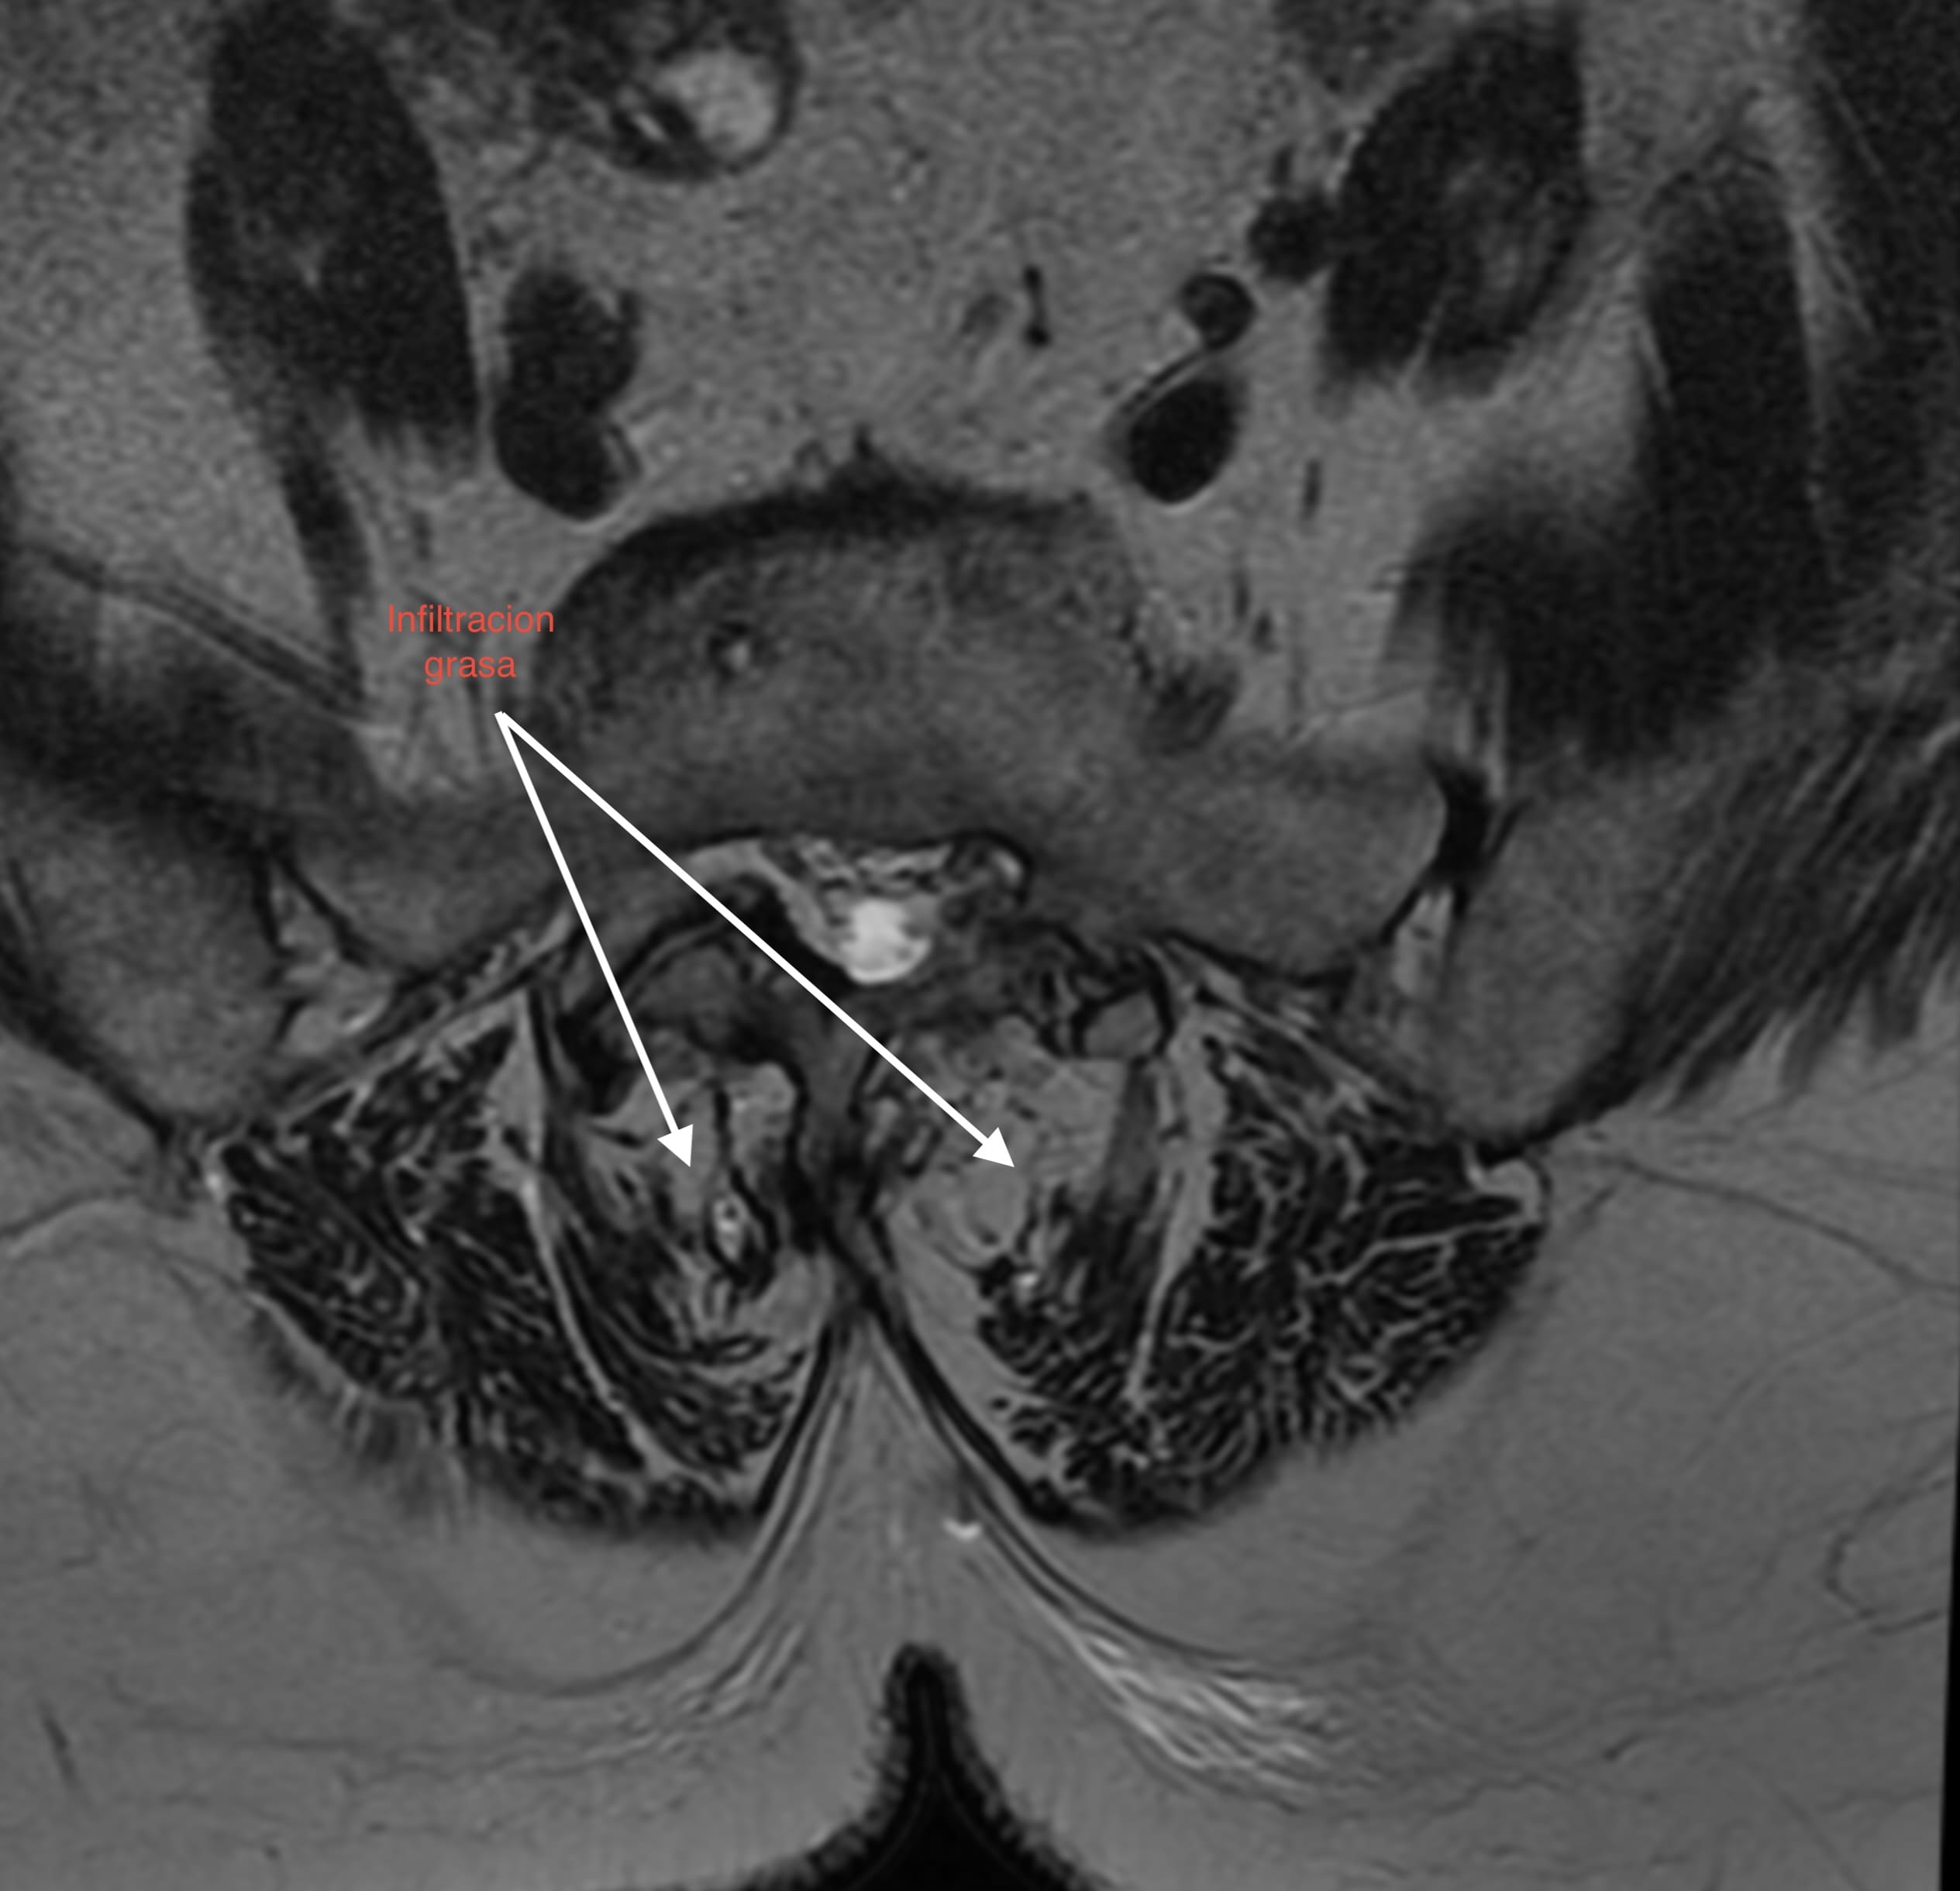

1. Pérdida del «Tirante» Dinámico: Los músculos multífidos actúan como estabilizadores segmentarios finos. En pacientes sarcopénicos, estos músculos son reemplazados por tejido adiposo no contráctil, perdiendo su capacidad de tensión.

• Calidad vs. Cantidad: La infiltración grasa (clasificación de Goutallier o medición de unidades Hounsfield en TAC) en el multífido es un factor de riesgo independiente para la reintervención. Músculos con alta infiltración grasa se correlacionan con peores resultados funcionales (ODI) y mayor tasa de complicaciones mecánicas como la cifosis de la unión proximal (PJK).

1. Screening Preoperatorio Rutinario: La RM lumbar debe utilizarse para evaluar la calidad muscular (corte axial en L3/L4), no solo la patología neural.

La sarcopenia y la infiltración grasa paravertebral no son hallazgos incidentales del envejecimiento, sino determinantes activos en la vida útil de una artrodesis lumbar. La atrofia muscular deja al disco adyacente desprotegido frente al estrés mecánico incrementado post-fusión. Identificar y tratar la sarcopenia es imperativo para reducir la incidencia de reintervenciones y mejorar la calidad de vida a largo plazo del paciente.